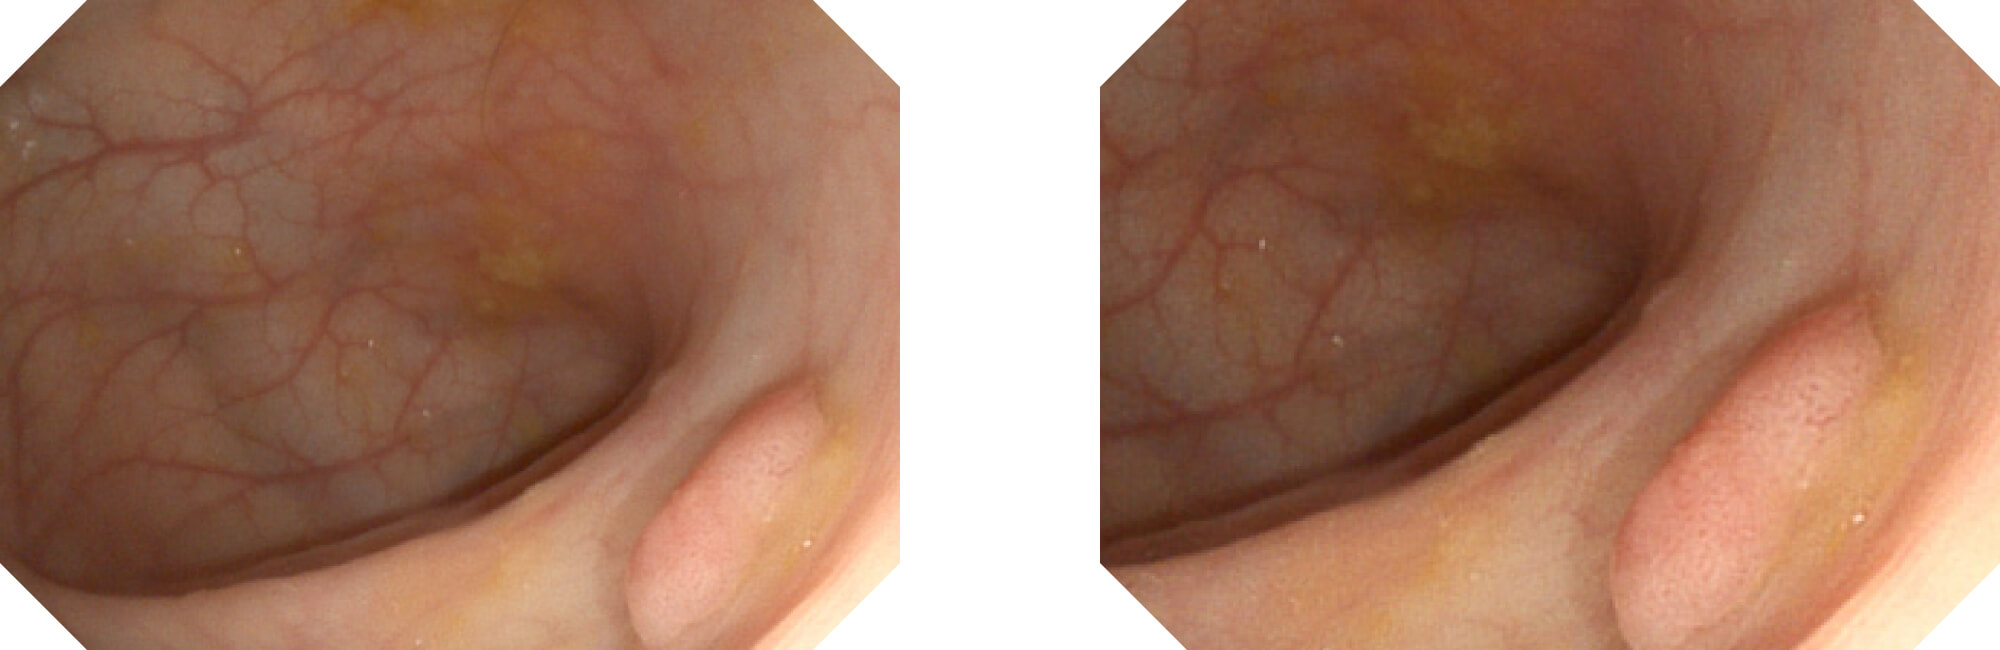

清晰视界,诊断胸有成竹

高清数字信号结合构造强调和色彩增强,多重图像处理技术能让每一个图像都清晰可见。

• 构造强调

• 色彩增强

• 电子放大